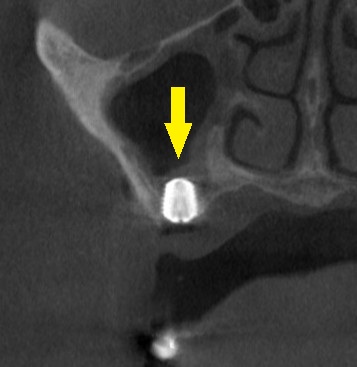

第一大臼歯には人工骨は使用せず、患者様ご自身の骨を上方に持ち上げ、ワイド径のインプラントを埋入する計画としました。

この方法で、患者様の了承が得られましたので、本日、インプラント埋入手術を施行しました。

下の写真下段が、手術後のCTです。